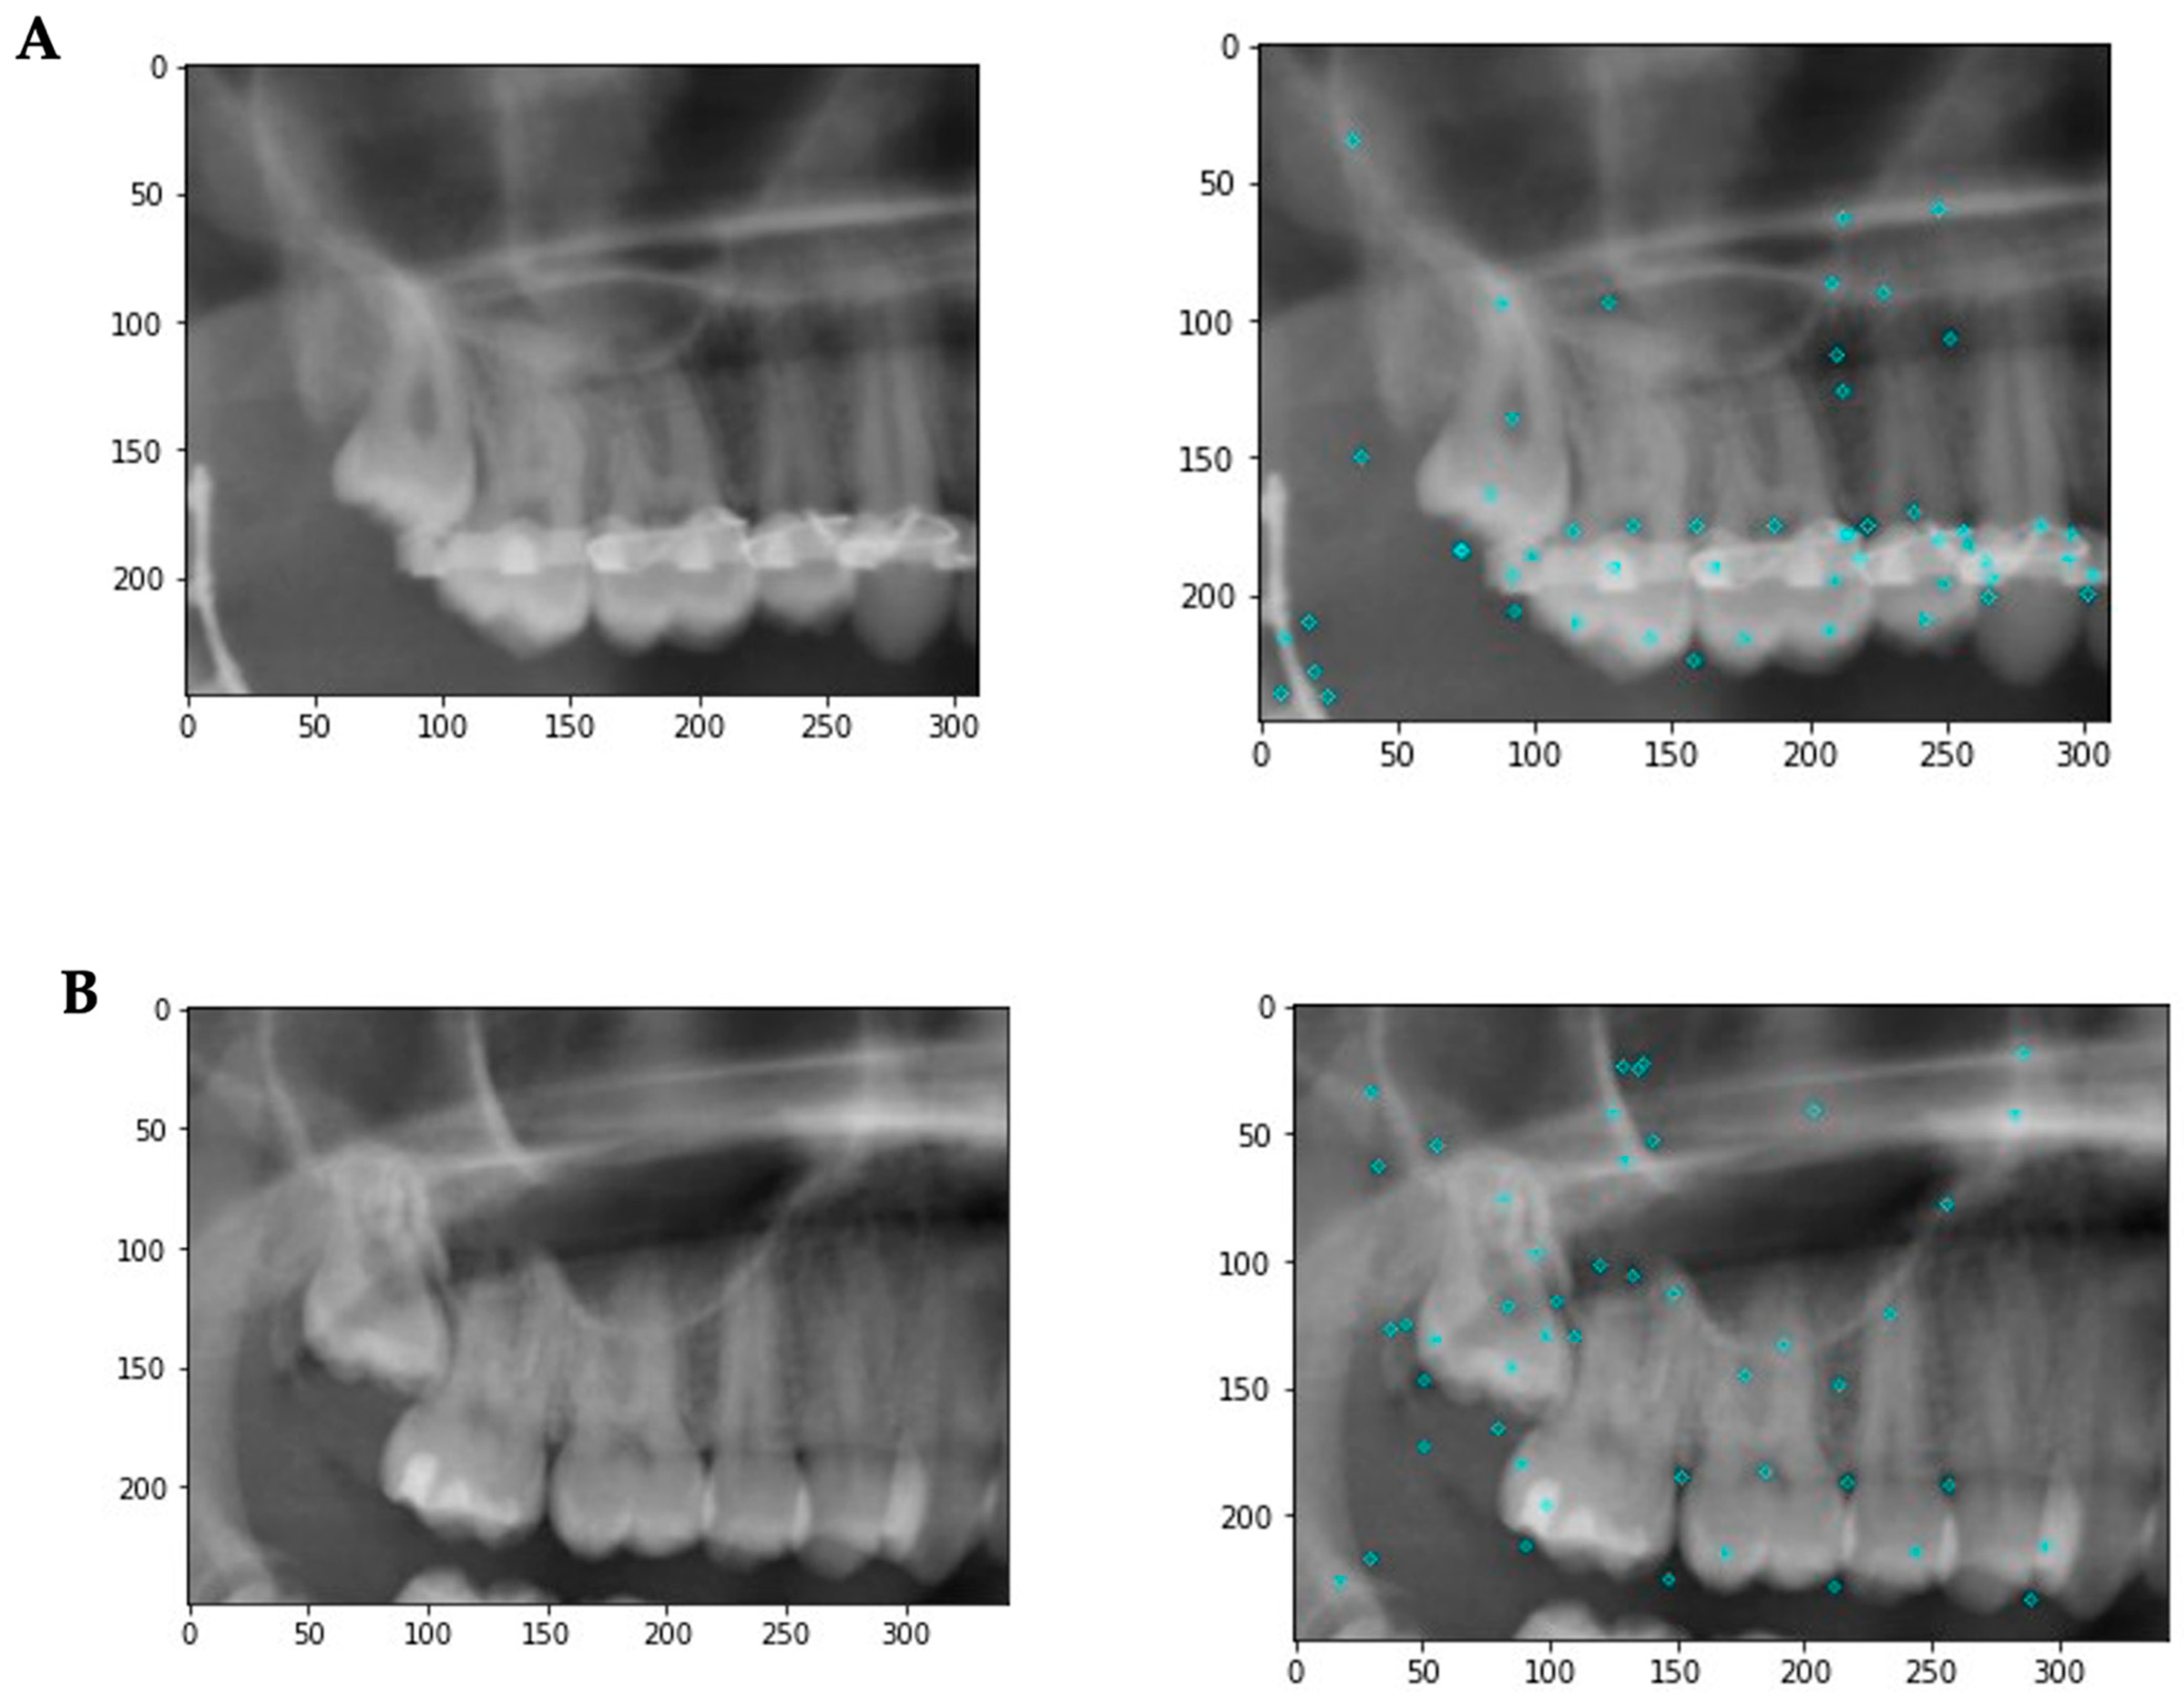

As part of the Bags of Visual Words (BoVW) technique, feature extractions from the input images were saved as BoVWs to prepare for training a model. As a general rule, a keypoint is a particular structure that contains several attributes, such as its coordinates (x, y), the meaningful neighborhood’s size, the angle that specifies its orientation, and the response that defines the strength of the keypoints, etc. Scale Invariant Feature Transform (SIFT) was used to extract the keypoints and descriptors. To create visual vocabularies for the BoVW, all extracted descriptors were clustered using K-Means clustering. The BoVWs were then fed into a support vector machine (SVM) model to predict the Archer and RS classes (Figure 2 and Figure 3).

Figure 2.

Application of the Bags of Visual words technique on dental X-rays to predict the RS and Archer class of third molar impaction. Keypoint is detected based on image features. A keypoint is a particular structure that has many attributes such as its (x, y) coordinates, size of the meaningful neighborhood, the angle that specifies its orientation, response that specifies the strength of keypoints, etc. Keypoints and descriptors are then extracted by Scale Invariant Feature Transform (SIFT). All extracted descriptors are then clustered using K-Means to obtain visual vocabularies for the BoVW. Finally, we fed these BoVW into a support vector machine (SVM) model to make the prediction of the Archer and RS classes and to evaluate the model based on the true labels (ground truth).

Figure 3.

Example images illustrating some of the image features. (A) Patient has metallic artefacts affecting the keypoint detection and subsequent classification. In addition, other structures such as endodontic fillings, crowns, composite fillings, etc., might affect the classification. (B) A situation with fewer artifacts. The keypoints are more evenly distributed with a focus on the third molar region.